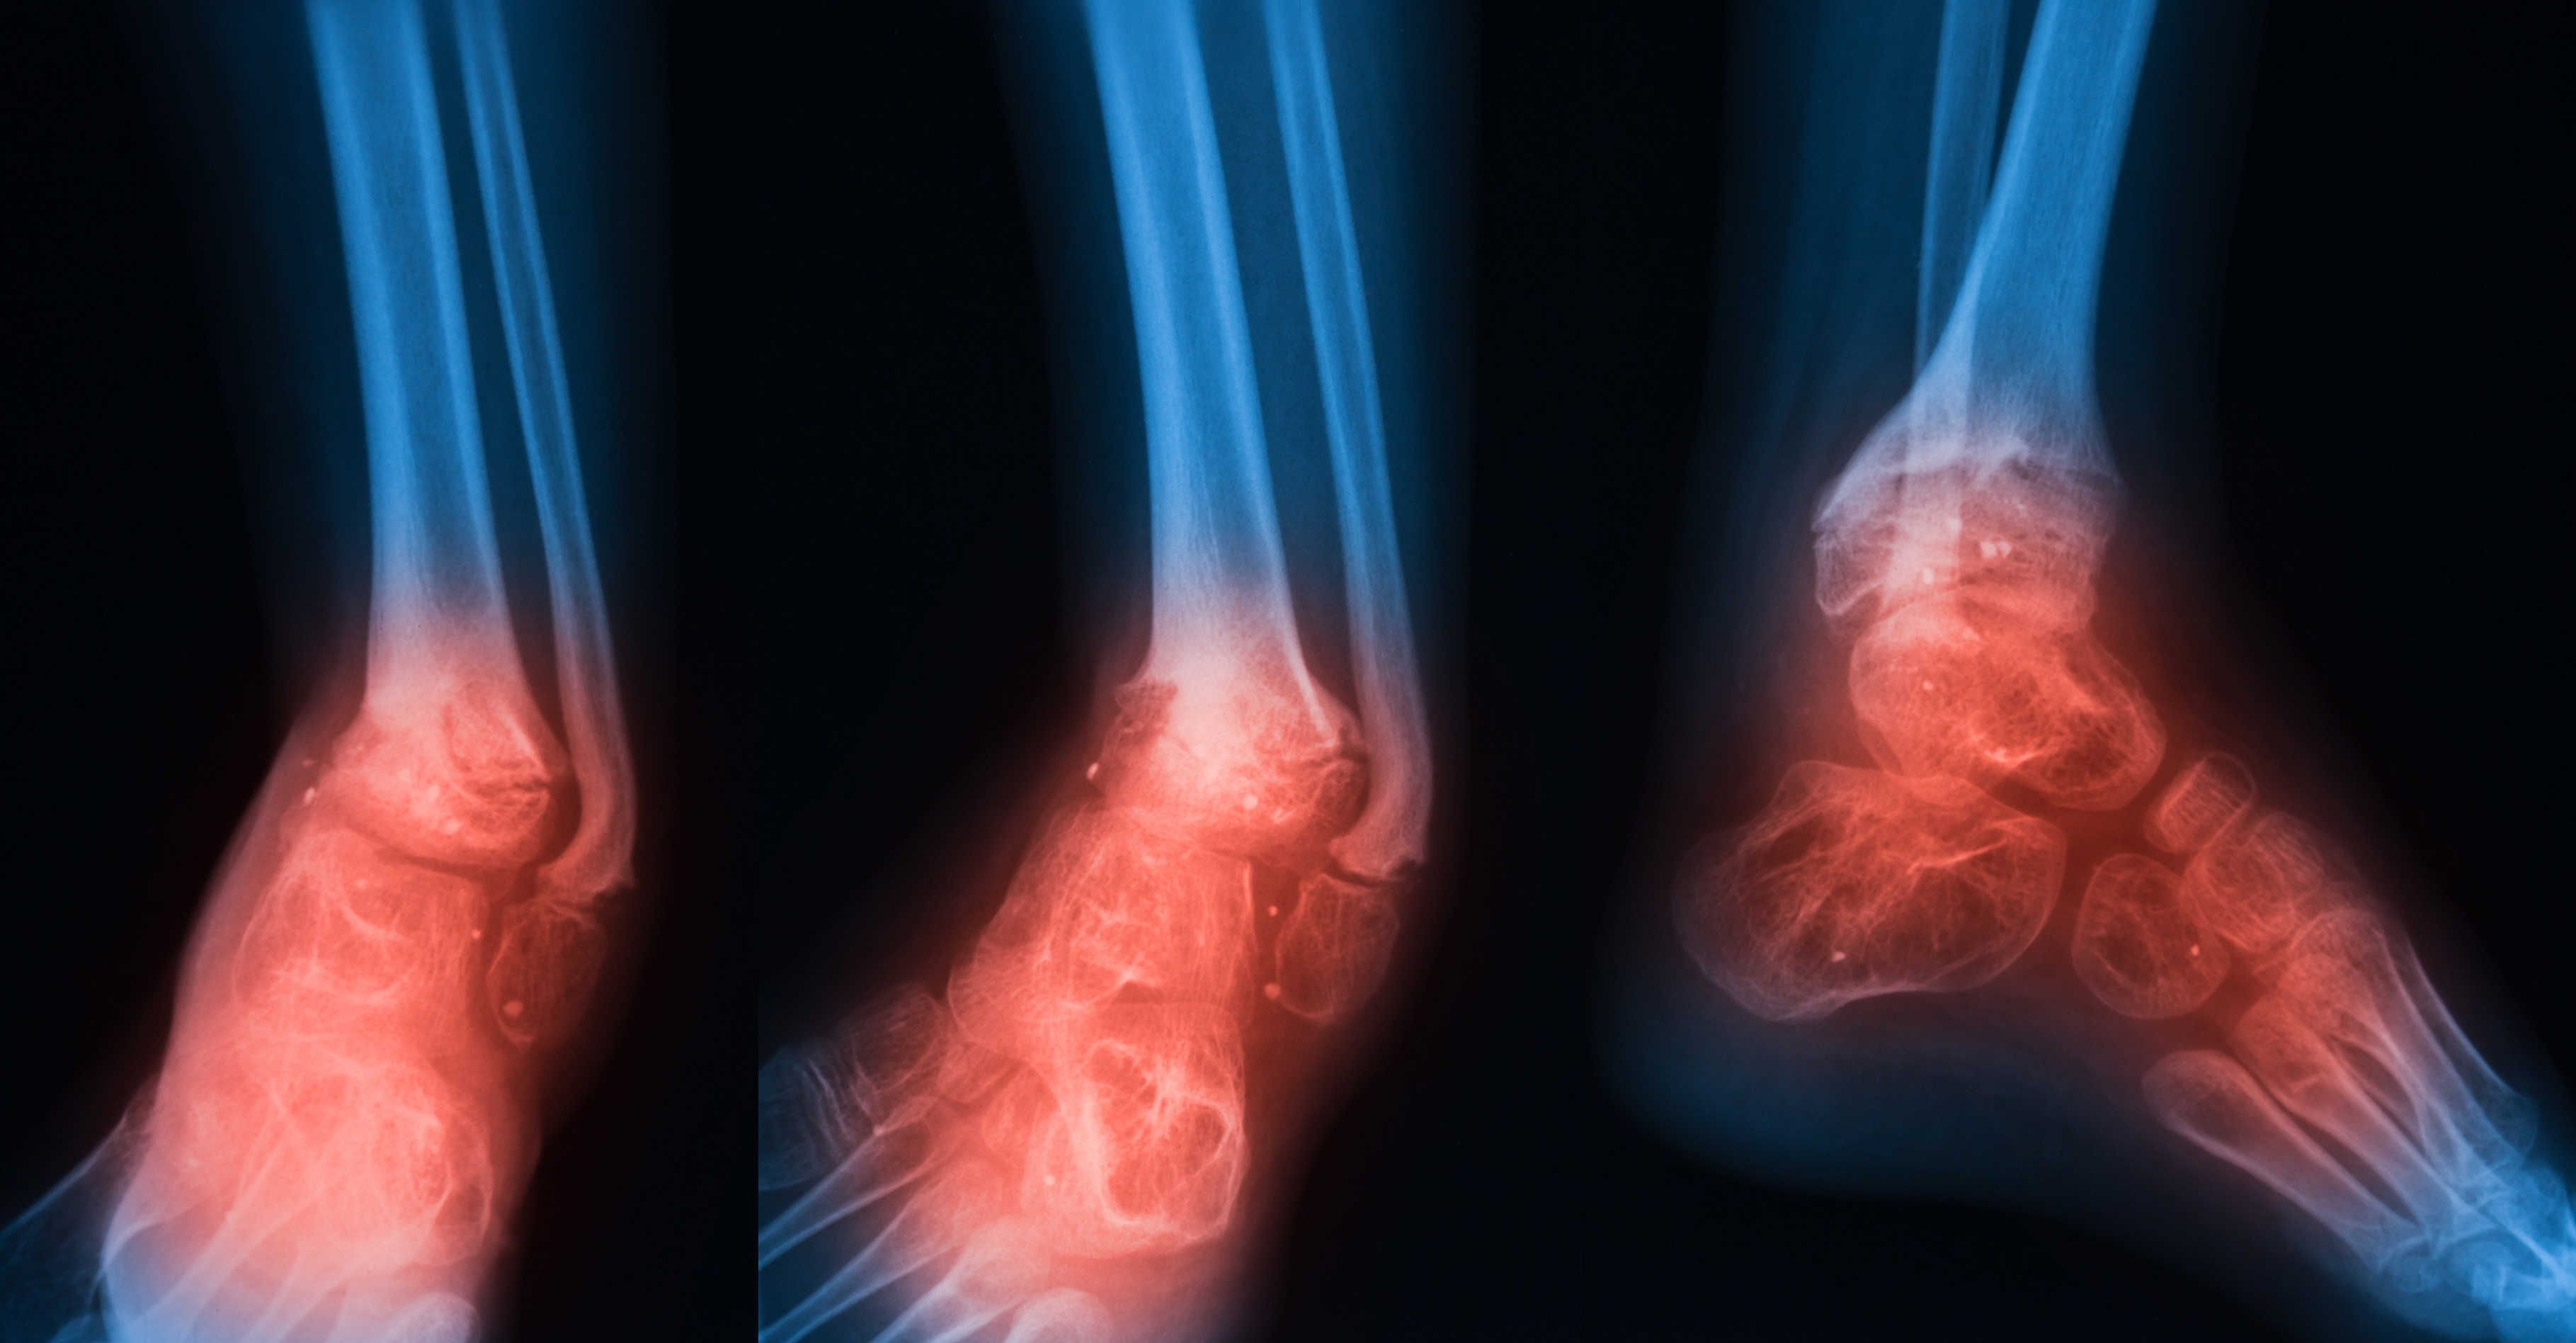

Osteomielitis adalah jangkitan tulang yang jarang berlaku tetapi serius. Jangkitan tulang boleh menjadi akut atau kronik. Jika pesakit tidak mempunyai rawatan yang betul, tulang tertentu boleh rosak secara kekal. Ia disebabkan oleh bakteria atau kulat yang menyerang tulang. Pada kanak-kanak, tempat yang paling popular di mana jangkitan tulang berlaku adalah pada tulang panjang lengan dan kaki. Sebaliknya, jangkitan kelihatan pada pinggul, tulang belakang, dan kaki.

Simptom jangkitan tulang

Biasanya, tapak jangkitan boleh mengalami kesakitan pada mulanya. Tanda-tanda umum yang lain adalah:

- Kemerahan di kawasan yang dijangkiti

- Bengkak di kawasan yang terjejas